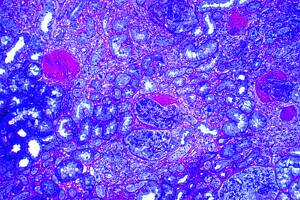

Fig# 12. GNPP III. CA3, CC1 (OMS IVC?):

GNPP III con trombosis, necrosis, proliferación celular. Fibrosis temprana <25%. MOAR 200 X.